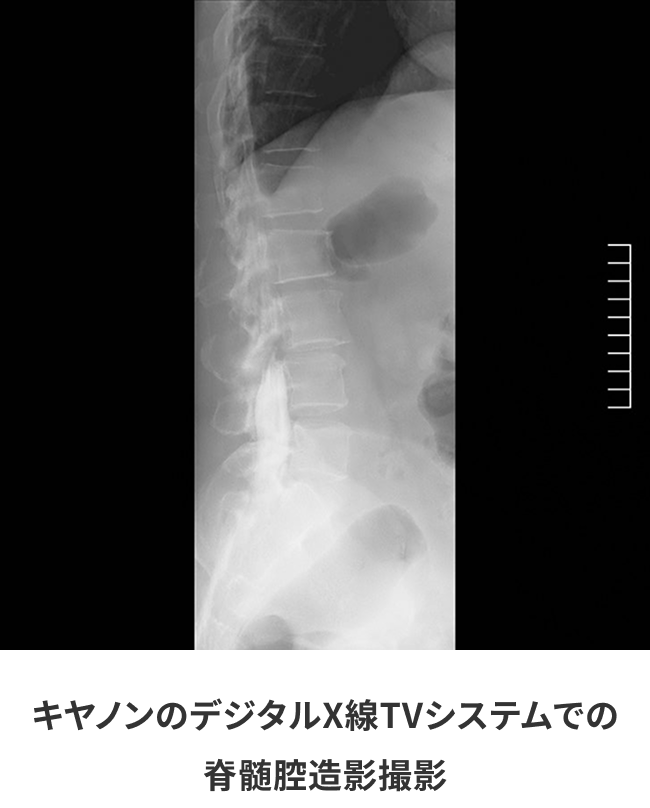

同一患者における一般撮影とキヤノンのデジタルX線TVシステムとの画像比較

検査室に以前設置されていたX線TVシステムでは、画質を求めると線量を上げなくてはならず被ばく量が増えてしまうため、線量をおさえると細かいところまで確認ができないという悩みを抱えていました。

17インチx17インチのデジタルX線検出パネルと新開発の画像処理装置といった、これまでキヤノンが培ってきた技術の組み合わせによって透視画像のノイズ低減とコントラスト分解能が向上し、高画質化を実現しながら従来機種と比べ線量低減を実現しています。